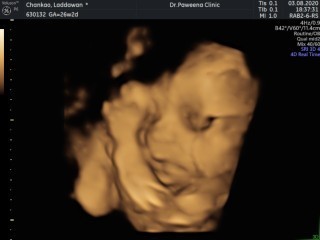

26+5ลูกสาวจ้า อิจฉาแม่จัง ของบ้านนี้น้องไม่ยอมให้เห็นหน้าตอนซาว4มิติ ได้เห็นแต่เพศน้องอย่างเดียว😂😂

26+2ค้าบ ลูกชายลูกคนแรกเหมือนกันจ้าแม่นี้ตื่นเต้นมาก🥰

28 ปิดหน้าปิดตาครับ ขี้อาย🤦♀️🤦♀️🤦♀️

26วีค6วันคะ กำหนดคลอด 22 /พ.ย./63 ลูกคนแรกจ้า

27w3d ค่ะ กำหนดคลอด 18 พ.ย. 63 สาวน้อยจ้าา

26 วีค ลูกคนแรก ผู้ชาย เหมือนกันเลยค่ะ